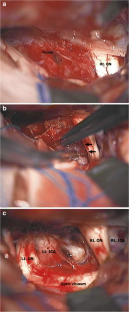

Fig. 1

Fig. 2